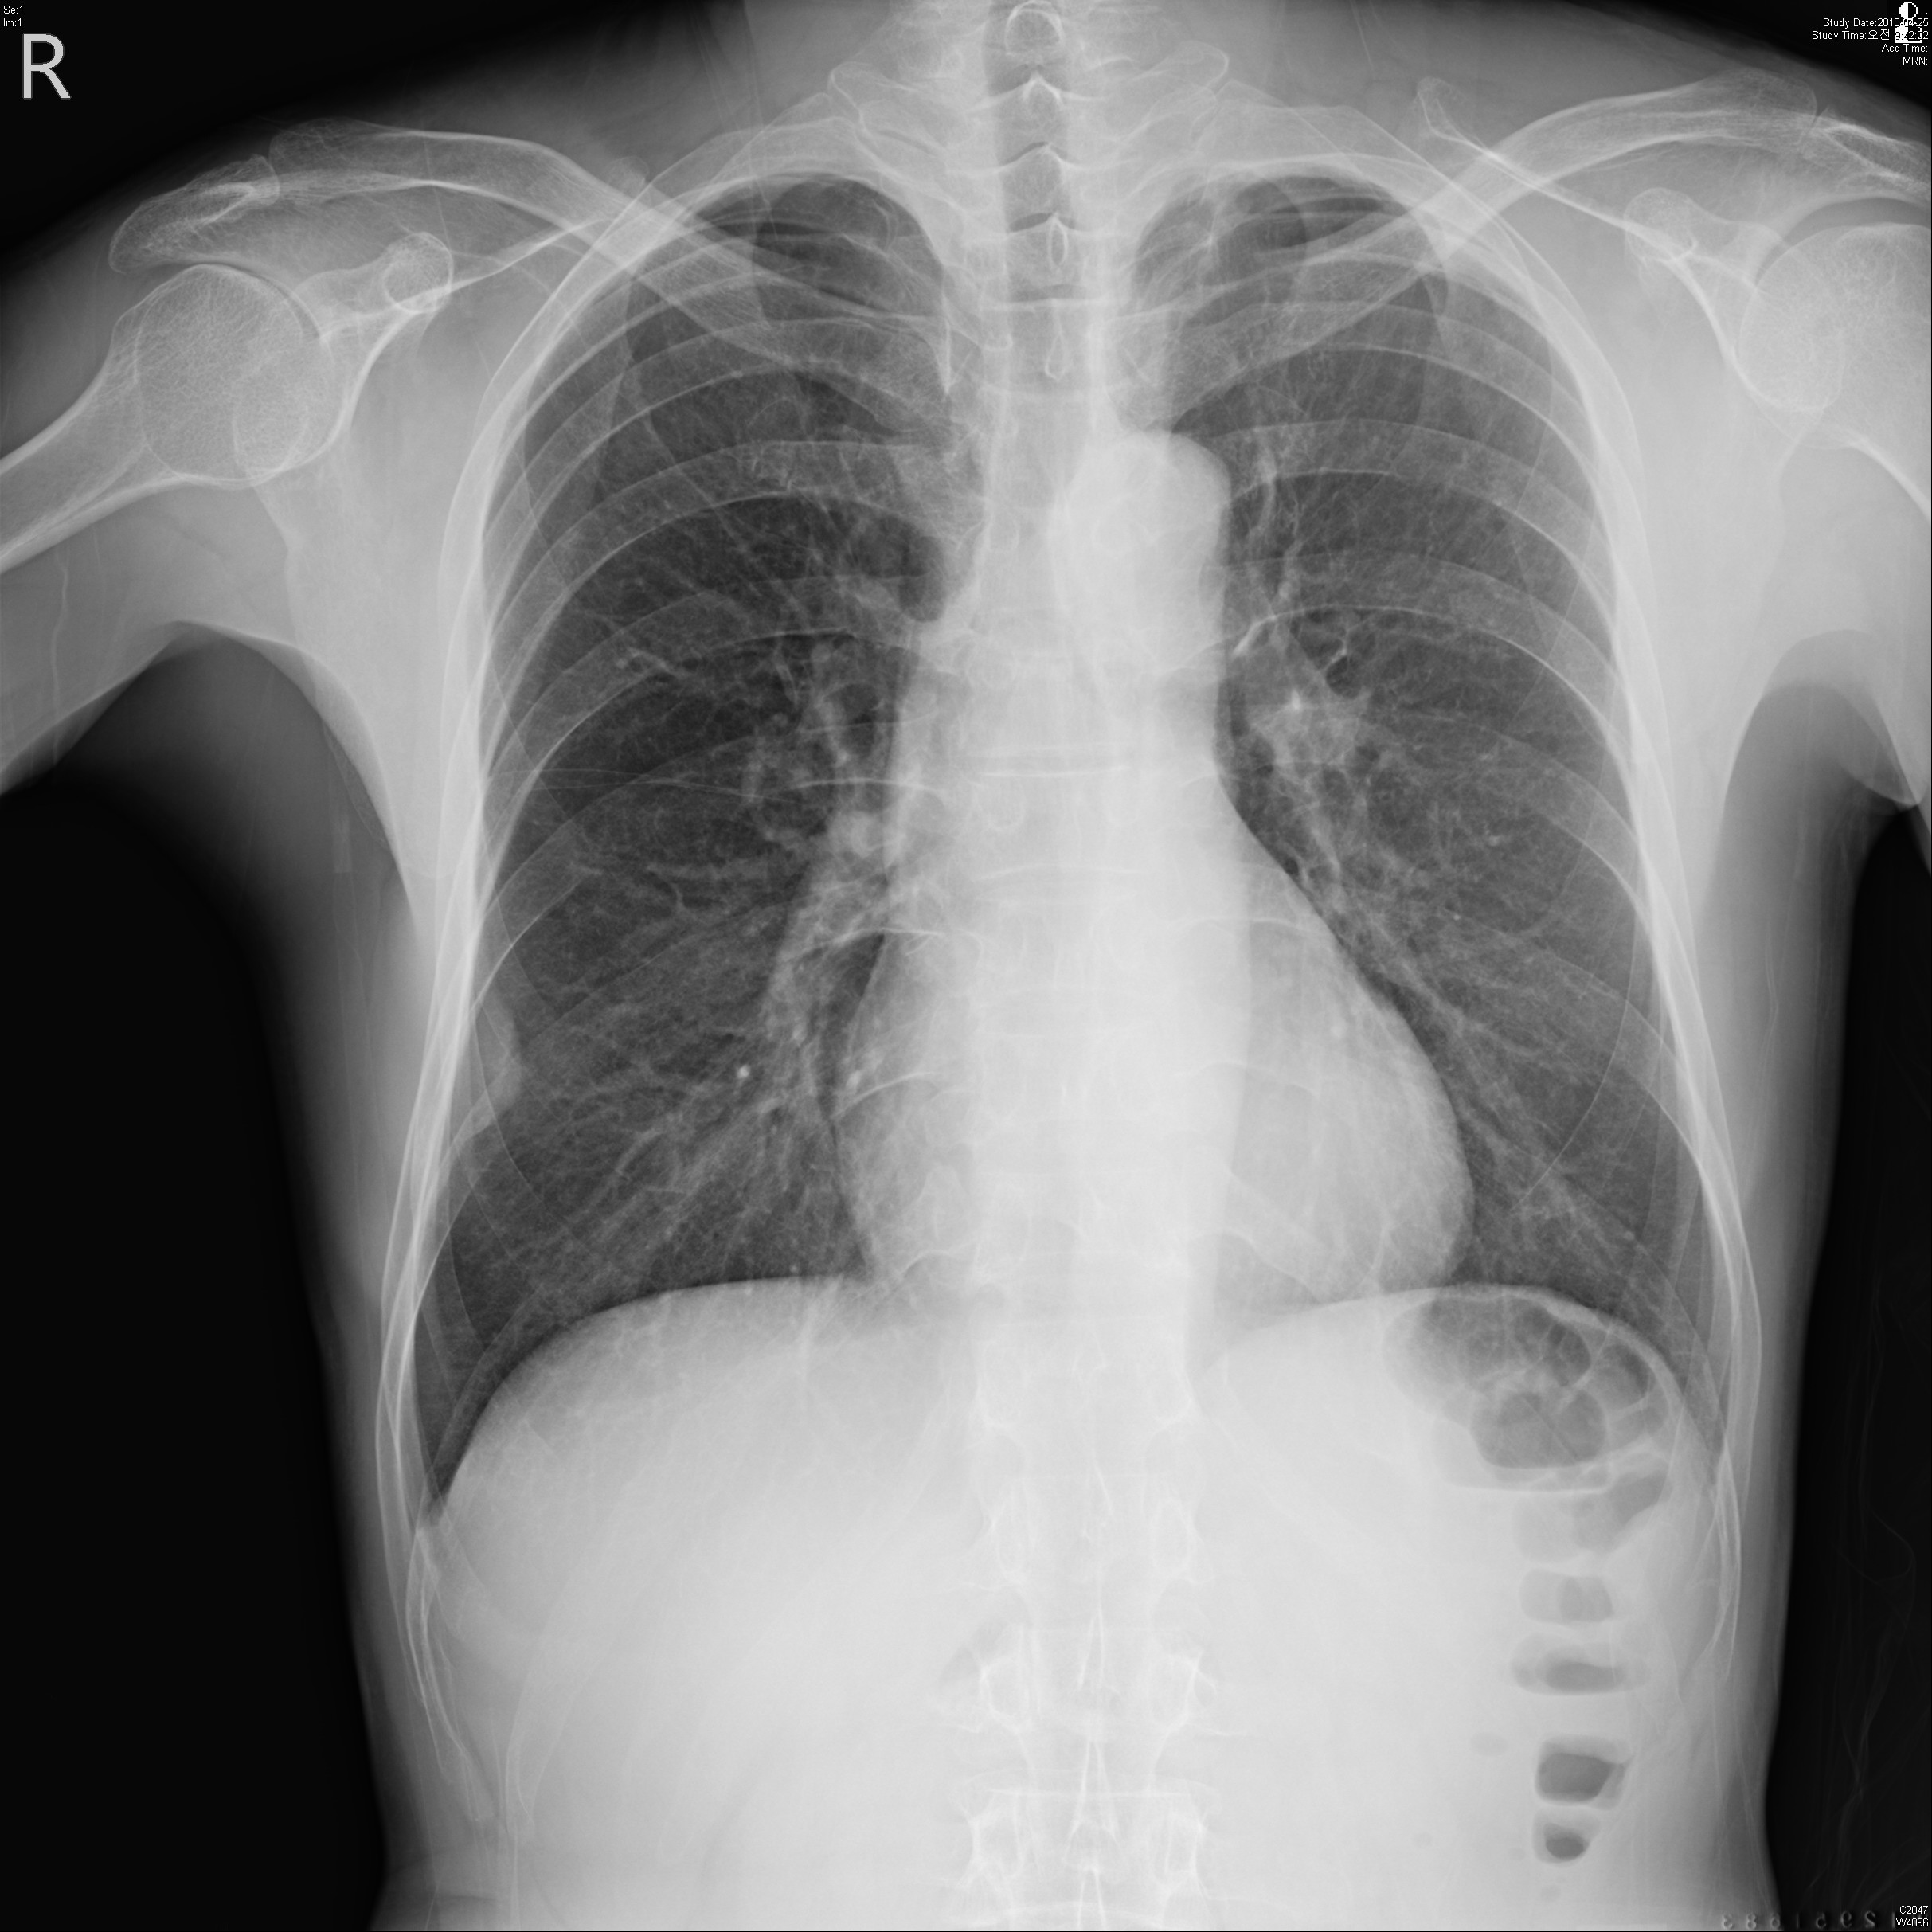

59¼¼ ³²È¯ ƯÀÌ ³»°úÀû °ú°Å·Â ¾ø´ø ȯÀÚ·Î °Ç°­°ËÁøÀ¸·Î ½ÃÇàÇÑ CxR »ó ÀÌ»ó¼Ò°ßº¸¿© refer µÈ ȯÀÚÀÔ´Ï´Ù.

³»¿ø´ç½Ã ƯÀÌ Áõ»ó¾ø¾ú°í,³»¿ø ´ç½Ã lab °ú CxR,chest CT ´Â ´ÙÀ½°ú °°½À´Ï´Ù.